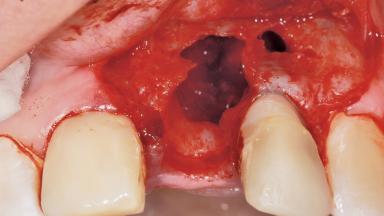

Late Placement of an Implant in a Maxillary Left Central Incisor Site

Bone Augmentation Horizontal|Staged

Augmentation Materials Xenogenous|Membrane

Soft Tissue Grafting Simultaneous

Bone Volume Deficient horizontally, requiring prior grafting